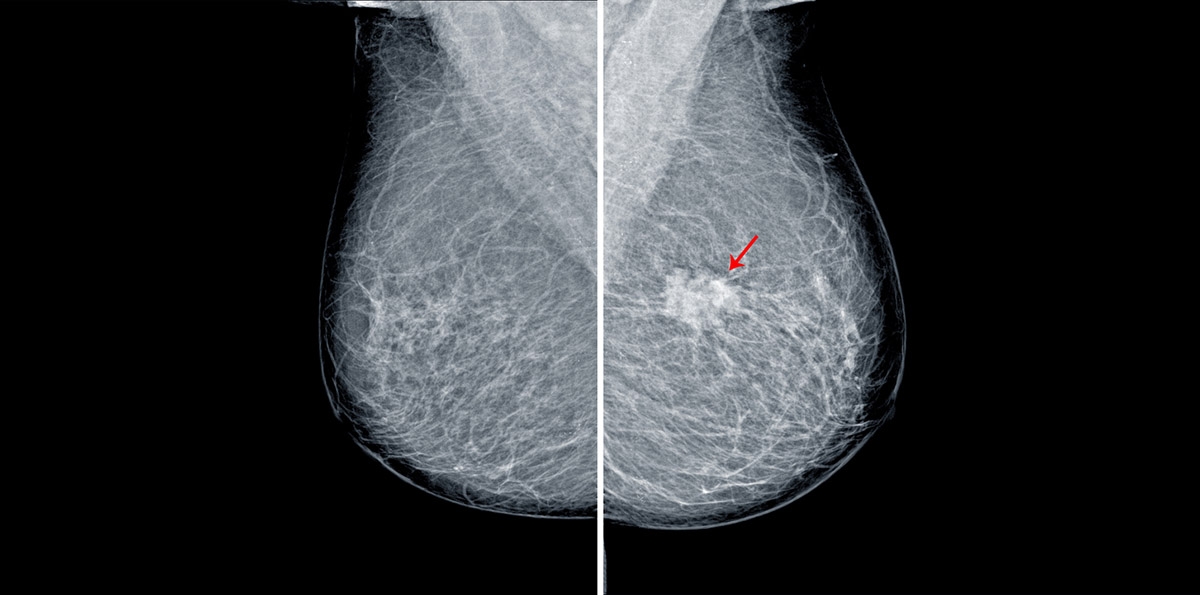

Οι εναποθέσεις ασβεστίου στις αρτηρίες του μαστού (επασβεστώσεις) είναι μία συνηθισμένη κατάσταση, ειδικά σε γυναίκες μέσης ηλικίας. Μπορεί να αιτιολογείται με πολλούς διαφορετικούς τρόπους (π.χ. ένας παλαιότερος τραυματισμός, κάποιες κύστες ή ιναδενώματα) και άλλοτε είναι καλοήθεις, ενώ άλλοτε ύποπτες.

Οι υποψίες έχουν να κάνουν με τον κίνδυνο καρκινώματος, όπως αναφέρει και ο χειρουργός μαστού Δρ Αναστάσιος Παπαδόπουλος, κάτι που θα κρίνει ο μαστολόγος, που θα κατευθύνει σε περαιτέρω διάγνωση. Αυτά τουλάχιστον γνωρίζαμε μέχρι σήμερα, γιατί ένα νέο συμπέρασμα προέκυψε από δύο ερευνητικές ομάδες που ανέφεραν στην ετήσια συνάντηση της Menopause Society στο Σικάγο το εξής: Η συσσώρευση ασβεστίου που ανιχνεύεται με τη μαστογραφία, συνήθως δεν είναι σημάδι καρκίνου, αλλά μπορεί να υποδηλώνει υψηλότερο κίνδυνο για καρδιακή νόσο.

Για να καταλήξει σε αυτό το συμπέρασμα, η μία από τις δύο ομάδες ακολούθησε για 18 χρόνια περίπου 400 γυναίκες και διαπίστωσε ότι η αθηροσκληρωτική καρδιαγγειακή νόσος (φραγμένες αρτηρίες που περιορίζουν τη ροή του αίματος) διαγνώστηκε στο 23% των γυναικών με ασβεστώσεις του μαστού, σε σύγκριση με το 13,9% που δεν είχαν.

Σε ξεχωριστή έρευνα, οι επιστήμονες του Penn State College of Medicine στην Πενσυλβάνια εξέτασαν δεδομένα από εννέα προηγούμενες μελέτες, που αφορούσαν σχεδόν 47.000 γυναίκες οι οποίες παρακολουθήθηκαν για 12 χρόνια. Εκείνοι διαπίστωσαν πως οι ασθενείς με επασβεστώσεις στους μαστούς (οι οποίες εντοπίστηκαν στη μαστογραφία) διέτρεχαν αυξημένο κίνδυνο εγκεφαλικού επεισοδίου, καρδιαγγειακού θανάτου, αθηροσκληρωτικής καρδιαγγειακής νόσου και συμφορητικής καρδιακής ανεπάρκειας.